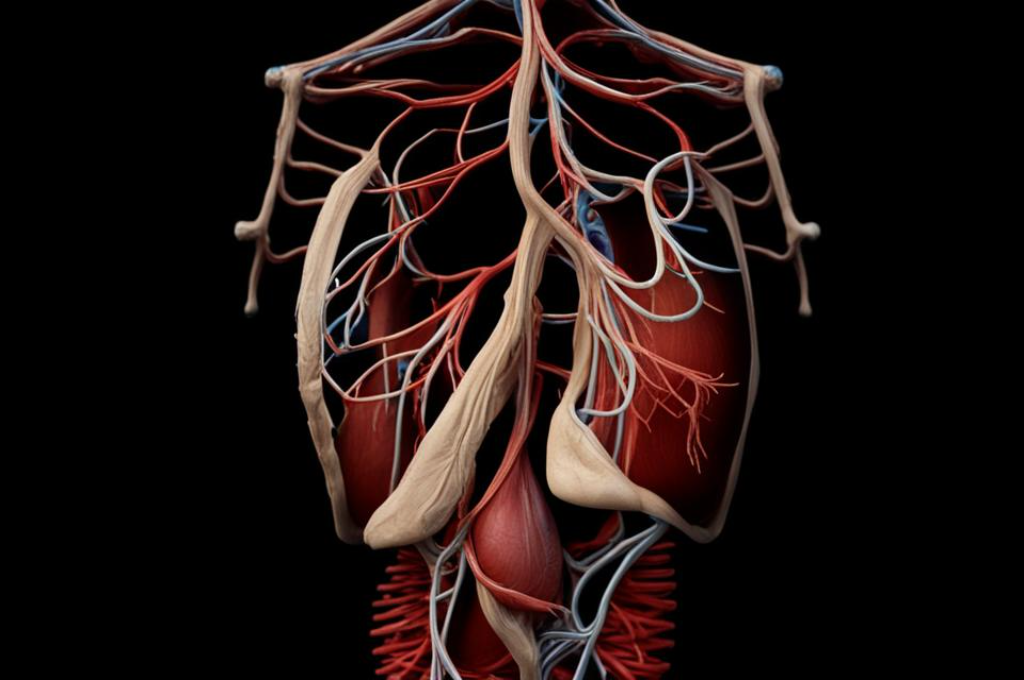

Чехонина выделила куриные сердечки как особенно полезный продукт, богатый витамином В12, необходимым для формирования эритроцитов, которые переносят кислород по всем органам. Она подчеркнула, что этот витамин также способствует укреплению костей.

Однако специалист предупредила о нецелесообразности употребления куриных сердец при определенных заболеваниях, таких как подагра, почечнокаменная болезнь и атеросклероз. В них содержатся вещества, которые могут ухудшить состояние здоровья при указанных заболеваниях из-за повышения уровня мочевой кислоты и насыщенных жиров.